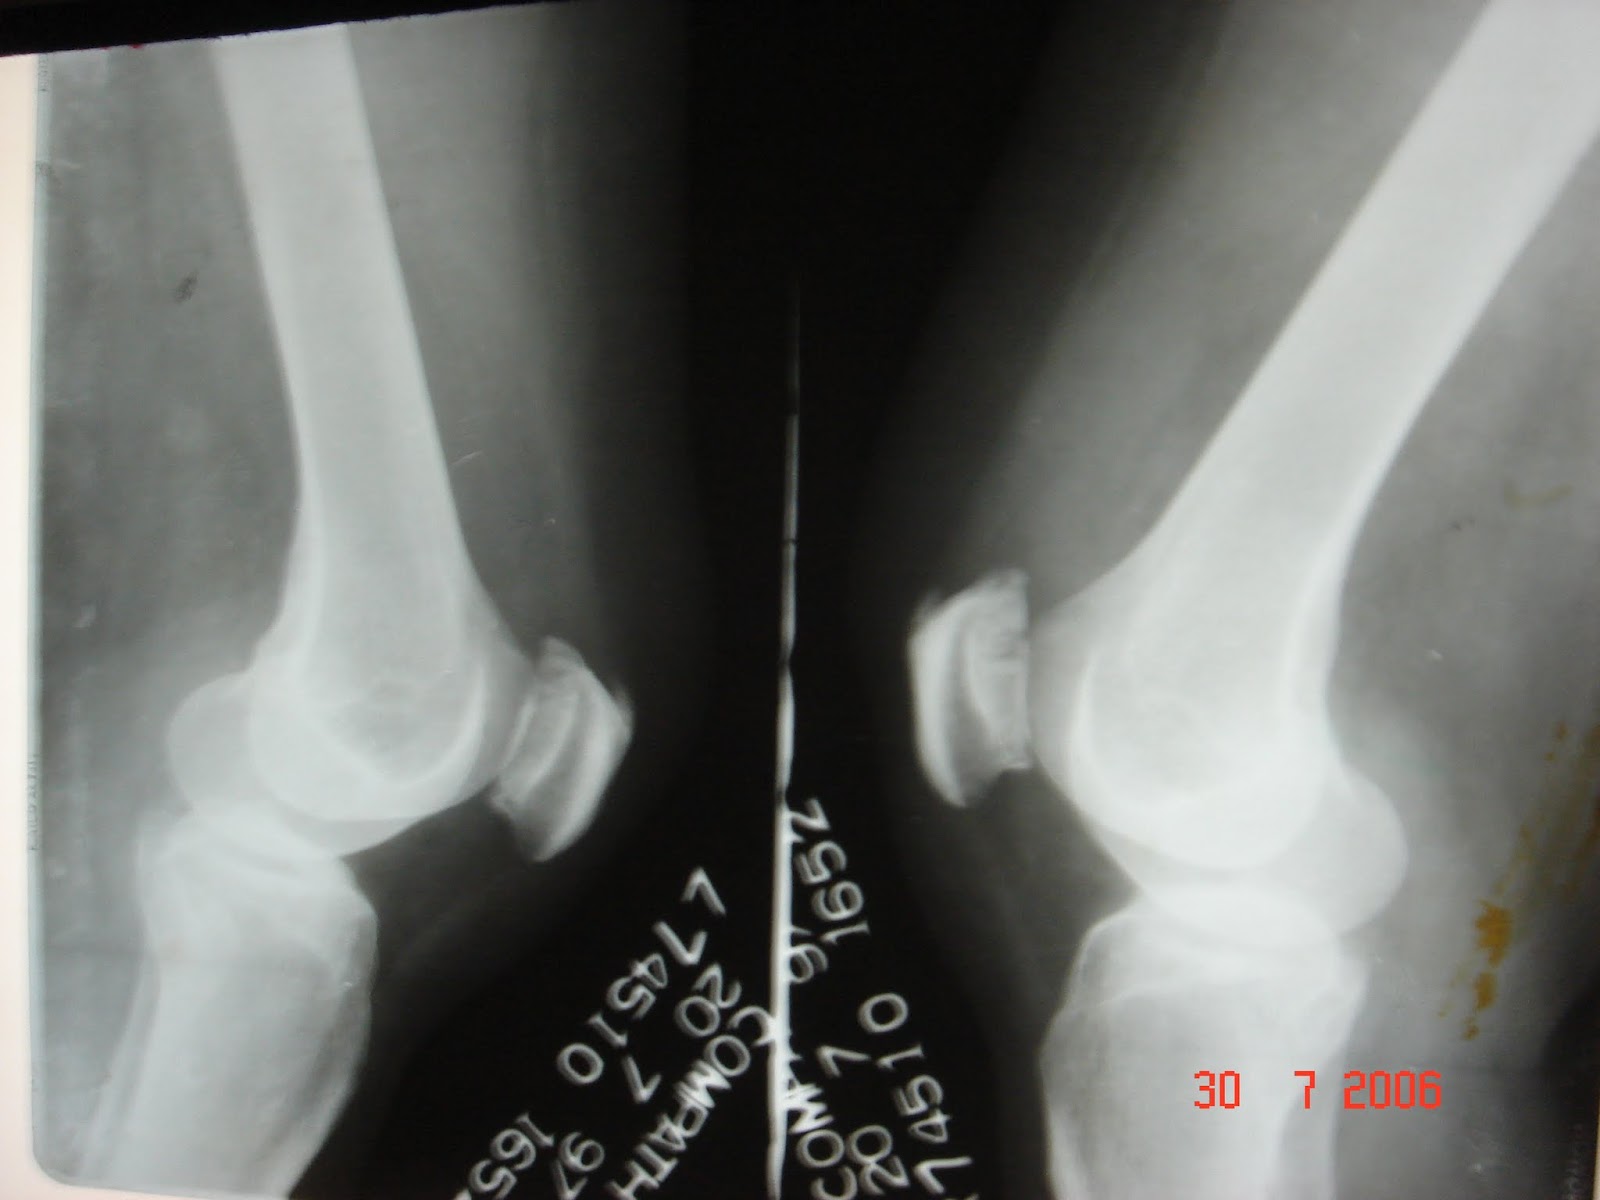

Xrays and Slides chondromalacia patella

Xrays and Slides chondromalacia patella Chondromalacia Patella X-Ray An ap view of the patellofemoral joint is needed to detect any radiological change. It is like a softening or. Softening or wearing away of the patellar articular cartilage (chondromalacia patella) causes varying degrees of. Chondromalacia patellae is a condition where there is damaged cartilage behind the patella (kneecap). The classification was initially devised for chondromalacia patella grading. Idiopathic chondromalacia. Chondromalacia Patella X-Ray.